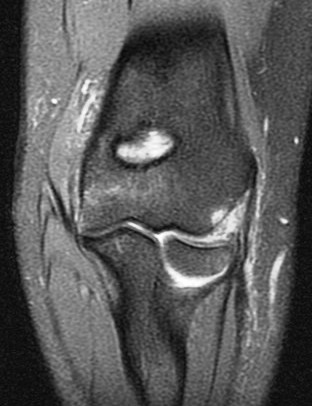

21 y/o F s/p wrestling injury. R/O acute radial head fracture.

Complex combination of valgus and varus stresses, probably a subluxation. Note the tear of the posterior lateral capsule just behind the ligamentous origin on the pdfs coronal. Patient should have posterolateral rotatory instability (PLRI). Also had extensor tendon strain with partial tear, trabecular injury of the coronoid process and of the humeral trochlea. Reference article.

Tear of combined origin of the lateral ulnar collateral ligament and radial collateral of elbow (RID2043)(RID2035)